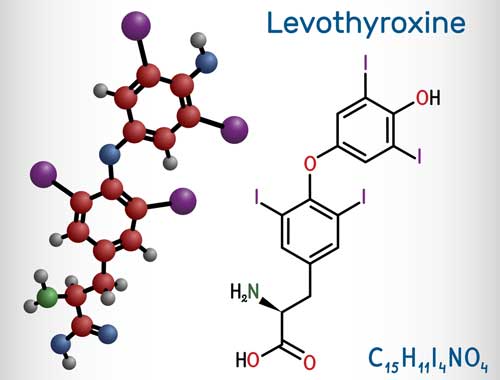

If you’re taking levothyroxine to manage hypothyroidism, you may have heard recent news linking this common thyroid medication to an increased risk of bone loss.

This medication, used by millions of people to regulate low thyroid hormone levels, was recently studied by researchers who found that prolonged use could potentially reduce bone density, especially in older adults. Click Here to read more on the study findings.

Let’s start with the basics: your thyroid plays a significant role in keeping your body running smoothly. When it’s underactive, as in hypothyroidism, medications like levothyroxine provide a much-needed boost of thyroid hormones.

However, like many treatments, this medication isn’t without its potential side effects. The recent study from Johns Hopkins Medicine suggests long-term use may be linked to bone density loss, especially in older adults. This means now is the perfect time to think proactively about your bone health and overall well-being.

Before diving into strategies, it’s important to understand how hypothyroidism and its treatment can affect your bones. The connection lies in your thyroid hormone levels. When these levels are too high—a condition called subclinical hyperthyroidism—it can accelerate the breakdown of bone tissue. This is why your medication dosage needs to be carefully balanced. Too much thyroid hormone can strain your bones, while too little can leave you feeling fatigued, sluggish, and unwell.